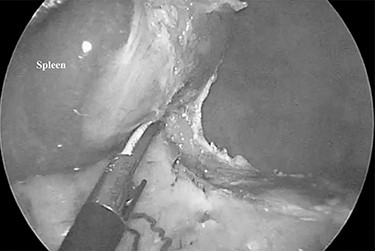

The patient was placed in the right lateral decubitus position. The standing positions of the surgeon and the assistant were on the right or left of the patient depending on the surgical site. Initially, a 12-mm port was introduced through the lateral margin of the left rectus abdominis muscle at the level of the umbilicus. After establishment of pneumoperitoneum with an intra-abdominal pressure of 10 mmHg, two 3-mm ports were inserted in the left upper quadrant at the subxiphoid and left subcostal margin along the mid-axillary line. The accessory spleen was carefully explored through the abdomen. The spleen was mobilized from the lower to upper direction. The initial dissection involved release of the lower pole of the spleen with dissection of the splenocolic ligament, and the spleen was freed from the splenorenal ligament toward the posterior aspect of the splenic hilus using laparoscopic coagulating shears under the guidance of a 3.3-mm needlescope (Karl Storz SE & Co. KG) (Fig. 2). Subsequently, short gastric vessels (Fig. 3) were divided, and the upper pole of the spleen was mobilized with the division of the splenophrenic ligament. Then, the splenic hilus was divided using a linear stapler (Fig. 4). The isolated spleen was then placed in an impermeable bag (Endo-Catch II; Covidien Co. Ltd.) and extracted via a 12-mm port after morcellation using the placenta forceps without extending the initial 12-mm incision (Fig. 5). After irrigation with normal saline and confirmation of hemostasis around the resected area without inserting a suction drain, only the 12-mm port site was only closed, and the 3-mm port sites were left open.

The spleen was freed from the splenorenal ligament using laparoscopic coagulating shears.